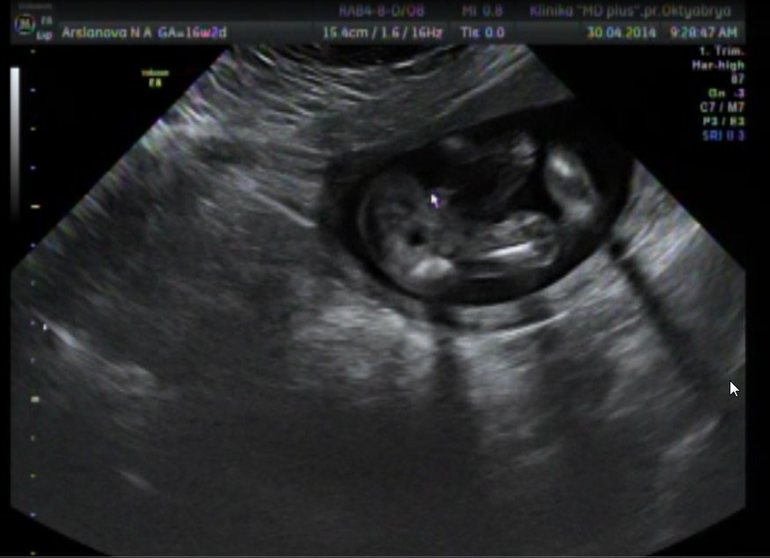

Записалась на УЗИ аж в 9 утра - ненормальная, итак не высыпаюсь.

На УЗИ я возлагаю большие надежды ) Прежде всего узнать пол человека - для мальчика у меня уже есть имя.

А кроме того, уже 17 неделя, а я этого тихушника совсем не чувствую. В совокупности с отсутствием живота, даже не верится что я беременна.